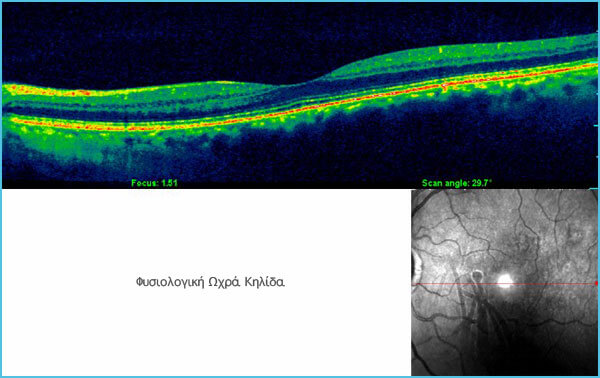

B. What is Optical Coherence Tomography (OCT)?

It is a painless examination , using a state-of-the-art machine, which analyzes the thickness of the retina and the macular area with an accuracy and resolution of 5 micromillimeters (5 μm) and with which we obtain a lot of information about both the extent and depth of the damage in the area of interest.

With this examination, we also monitor the improvement of the damage or the regression of the fluid in the macular area after treatment with intravitreal injection or photodynamic therapy.